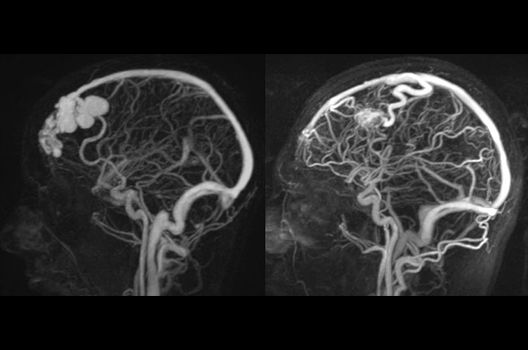

Die Magnetresonanztomographie (MRT) ist ein Verfahren, bei dem durch magnetische Kräfte Bilder des Körperinneren angefertigt werden. In der Neuroradiologie können manchmal kleinste Veränderungen schwere Folgen haben; daher forschen wir an der Entwicklung hochauflösender MRT-Sequenzen, mit denen diese Prozesse und auch einzelne Nervenfaserbahnen sichtbar gemacht werden können. Darüber hinaus sind bei vielen Erkrankungen des Gehirns die Blutgefäße betroffen. Daher arbeiten wir an der Neu- und Weiterentwicklung von MRT-Sequenzen zur Darstellung der Blutgefäße und zur Blutflussanalyse (sog. „Angio-MRT“). Einen besonderen Forschungsschwerpunkt unserer Klinik stellen die MR-Protonenspektroskopie und die funktionelle MRT dar, mit denen die Analyse einzelner chemischer Substanzen im Hirngewebe oder die Darstellung ausgewählter Hirnfunktionen möglich ist.

Interventionelle Neuroradiologie

- Behandlung intrakranieller Gefäßmissbildungen

In der Neuroradiologie sind wir häufig mit Fragestellungen konfrontiert, die mehrere Fachgebiete oder auch Methoden betreffen. So arbeiten wir auch in der Forschung intensiv mit anderen Abteilungen des Universitätsklinikums zusammen, um Prozesse und Techniken bei der Diagnostik und Therapie neurovaskulärer Erkrankungen und vaskulärer Anomalien zu optimieren.